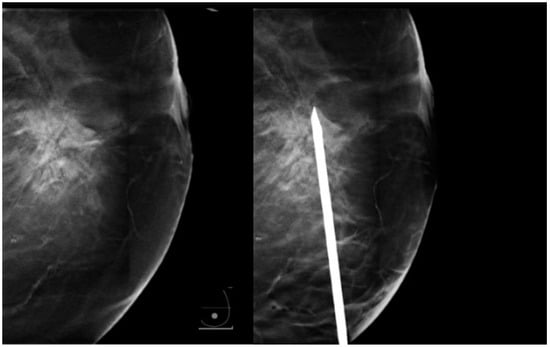

Figure 6. Biopsy needle parallel to the platform, avoiding the previously described artifact.

Figure 7. A spacer (arrows) can be positioned on the breast platform to allow elevation of the breast.